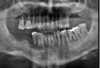

is the following periapical pathology or not?

yes

83

yes - root filled - PDL isnt continuous - lamina dura isnt continuous

no

85

86

yes - it is crowned - apical radiolucency - lamina dura tracking off

87

cant tell

88

89

yes - lamina dura tracking off

90

no PDL widened probs cus of brace

91